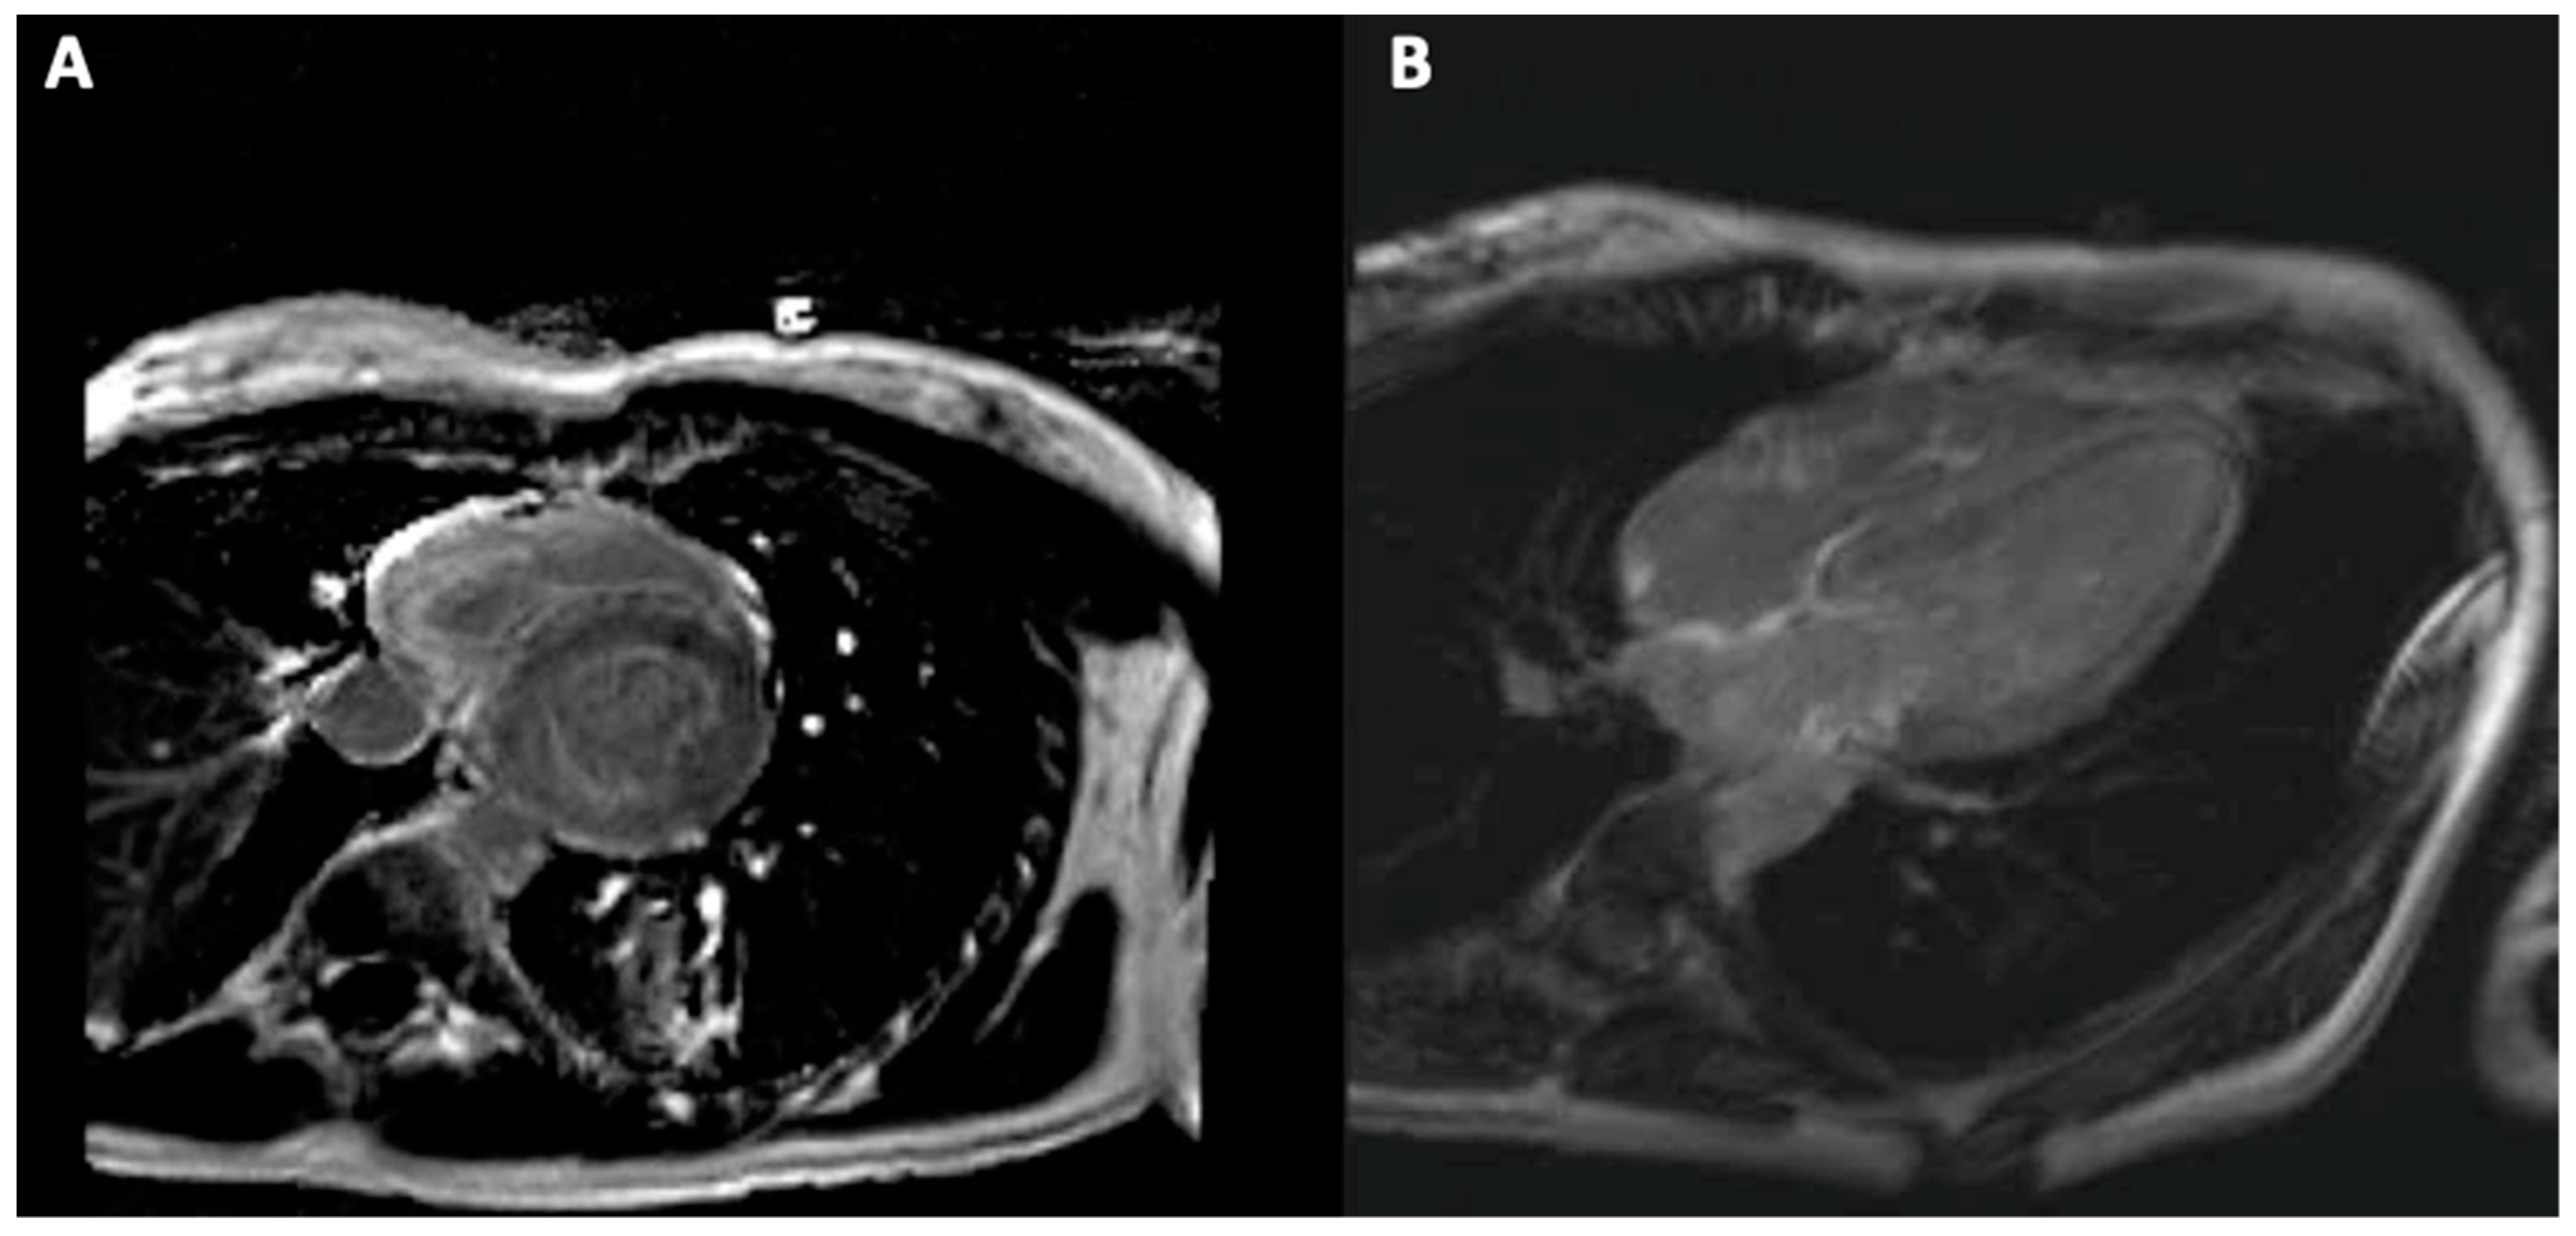

5. Cardiac Magnetic Resonance Imaging

5.2. Cardiac Magnetic Resonance Imaging in Sarcoidosis

5.3. Cardiac Magnetic Resonance Imaging in Hemochromatosis